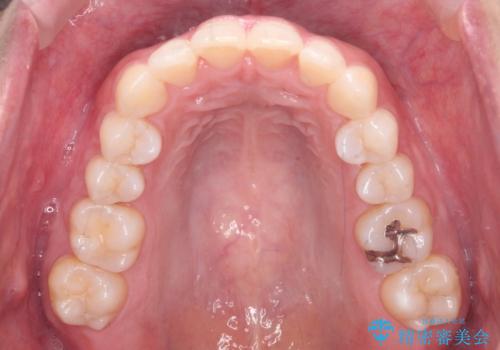

前歯をさげたい 歯を抜かずに マウスピース矯正で治したい

- 上の前歯が出ているとのことで来院。

歯を抜かずに、上の奥歯を後ろにさげつつ上の前歯を小さく少し削る処置を行い前歯の角度を修正しました。

右上下の奥歯もすれ違い咬合も、治療で改善しています。

下の前歯が生まれつき3本でしたので上下の正中は合わない仕上がりとなります。